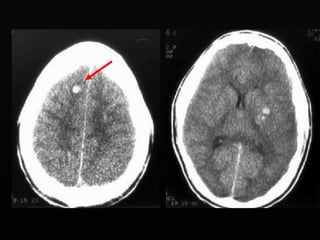

Jóvenes de 20 a 40 años Presentación aguda Fractura 90% Período lúcido de  6 a 18 hs en el 50% Temporal 90% Mortalidad 15-20% Bi convexo Hiperdenso Causas Laceración meníngea Fractura de calvario Sangrado arterial o sinusal Hematoma epidural

HED Biconvexo No pasa las  suturas Pasa la linea media